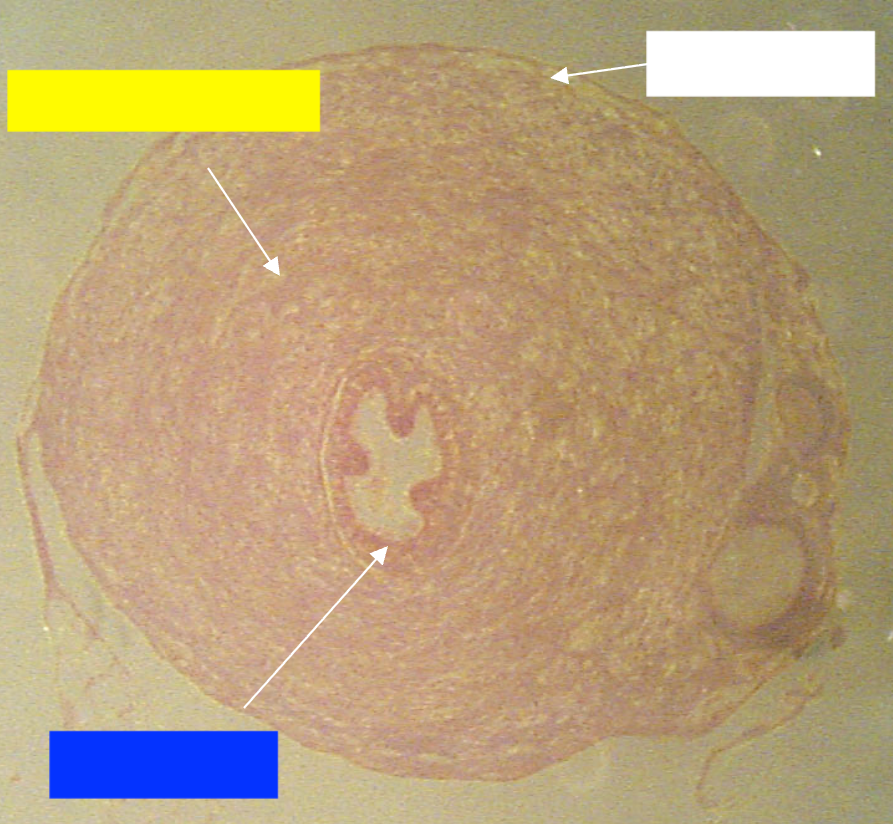

What is the name of the overall structure being depicted?

Vas deferens

Which layer of the vas deferens is being indicated by the white box?

Serosa

Which layer of the vas deferens is being indicated by the yellow box?

Muscularis

Which layer of the vas deferens is being indicated by the blue box?

Mucosa